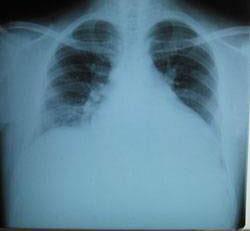

摘要:關(guān)于擴張性心肌病的最新治療,小巷深處的隱藏寶藏正逐漸為人們所發(fā)現(xiàn)。通過先進的醫(yī)療技術(shù)和方法,擴張性心肌病的治療取得了新的進展。這些治療方法旨在改善心臟功能,提高患者生活質(zhì)量。小巷深處的醫(yī)療機構(gòu)或?qū)<铱赡茈[藏著寶貴的治療經(jīng)驗和方法,為尋求最佳治療方案的病患帶來希望。更多詳細信息需要進一步探索和研究。